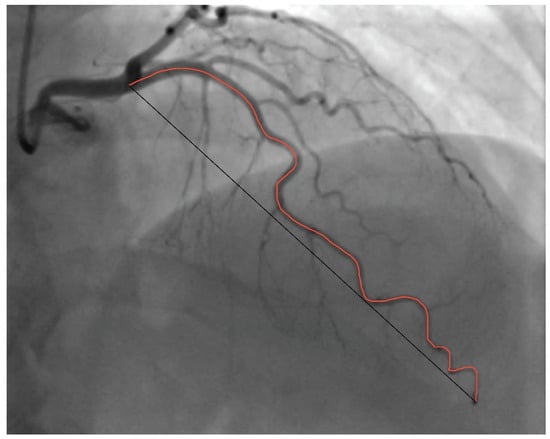

2. Materials and Methods